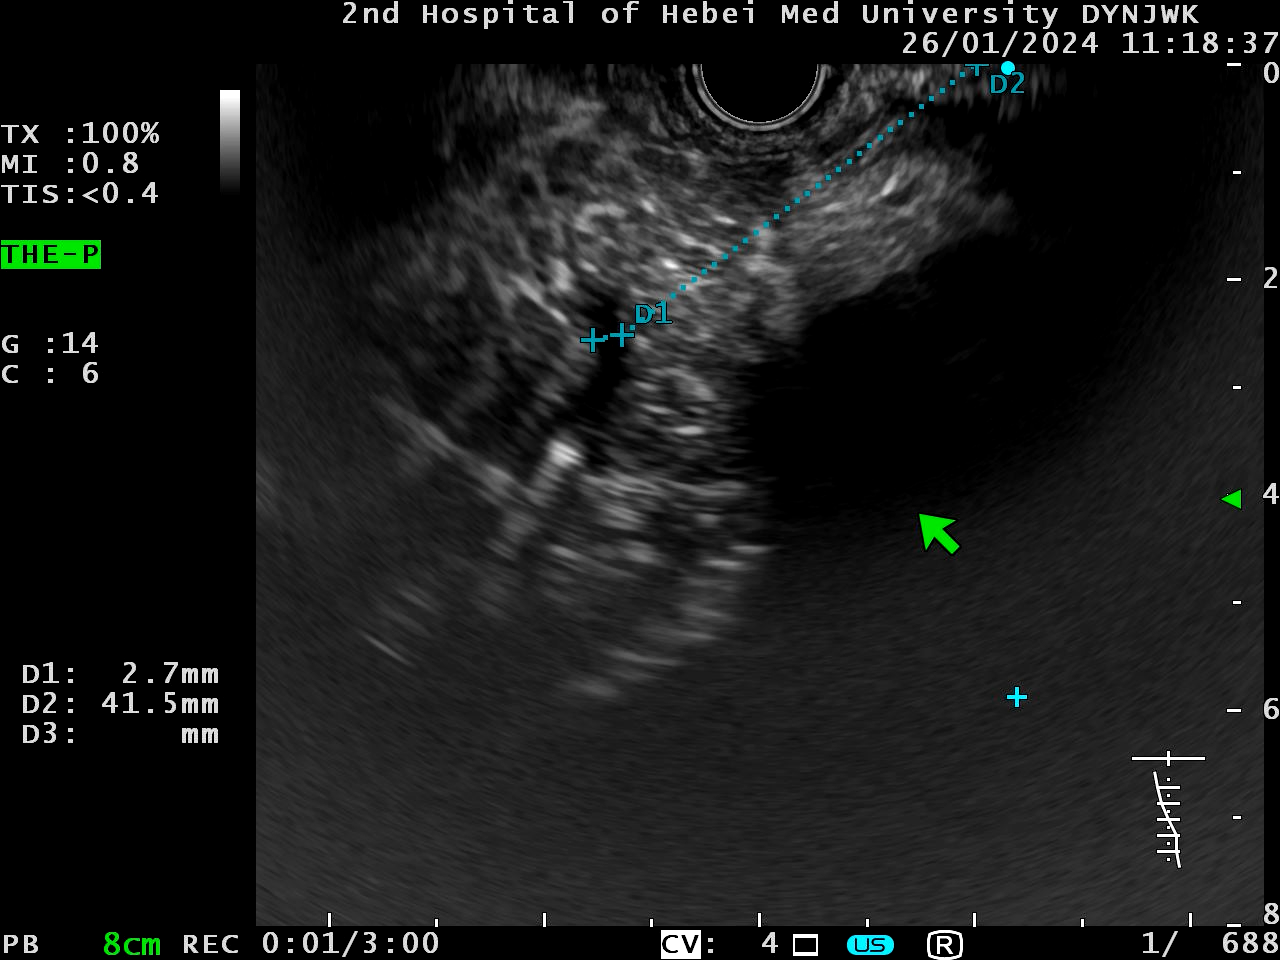

保留胃镜,进入超声内镜,找到胰管

微信图片_20241009155355.png

穿刺造影